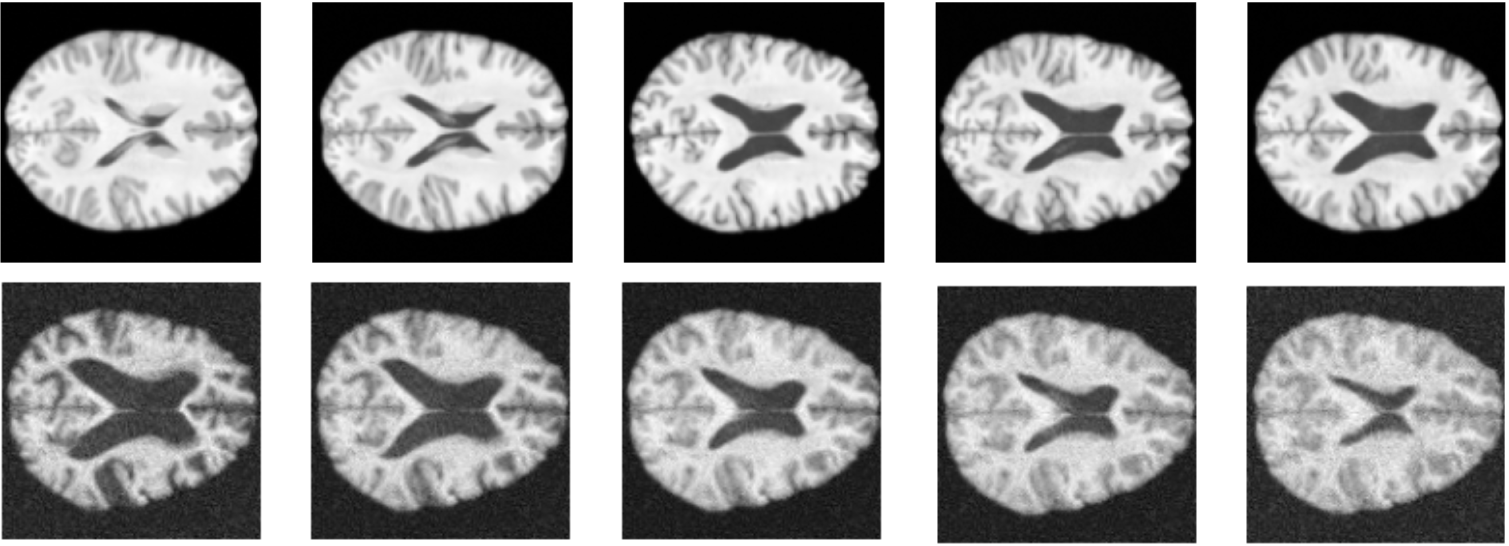

Appendix D Additional Results

Refer to caption

Figure 3: Age Interpolations. In the first row, the image in the first column is that of a 25-year-old, we then linearly interpolate between them and a 75-year-old (final column). The second row is the same but reversed, from age 92 to age 20. The difference in data quality, across the two rows, exemplifies the robustness of the model to varied data quality.